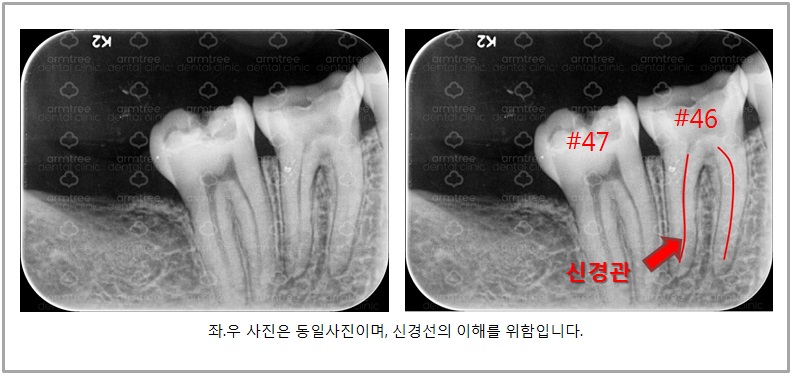

1번 사진] 환자 x-ray

환자분은 검사 결과 오른쪽 아래 6번과 7번 치아에 통증이 있었습니다. 그 치아로 인해 전체적으로 다 아픈 것처럼 느낀 것이었지요. 1번 사진 큰 엑스레이에 보시면 6번 7번 치아에 하얗게 예전에 치료한 흔적이 보입니다. 레진이라는 재료를 이용해서 충치 자리를 메꾼 것이지요. 그런데 아마 예전에 치료할 당시 충치가 크고 깊었을 것입니다. 충치가 깊으면 치료를 했어도 치아에게는 지속적인 자극이 될 수 있습니다.

그 자극으로 인해 치아가 아주 서서히 죽는(?) 경우가 있는데, 이 케이스가 그런 케이스입니다. 작은 엑스레이를 보시면 7번 치아는 안쪽에 신경이 선명하게 잘 보이는데 반해서 6번 치아는 신경이 잘 보이지 않습니다.

치아에 자극이 오랜 기간 가해지다 보면 치아가 스스로 보호막을 만드는데 그 과정에서 안쪽 신경이 좁아지거나 아예 막히는 경우가 있습니다.